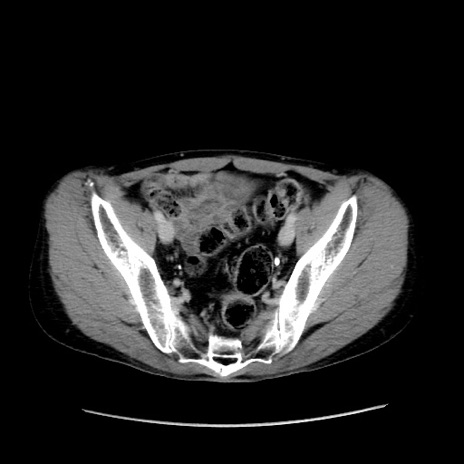

症例37(横断像)

【症例】40歳代 男性

【主訴】腹痛

【現病歴】4時間ほど前に電車に乗車中に臍部上より腹痛出現。徐々に増悪し起立困難となり、救急外来受診。生ものは数日食べていない。今朝お雑煮を食べた。

【身体所見】BT 36.8℃、BP 117/84mmHg、HR 91/min、SpO2 97%、苦悶様、腹部:臍上部広範囲圧痛あり、反跳痛±

【データ】WBC 8100、CRP 0.03